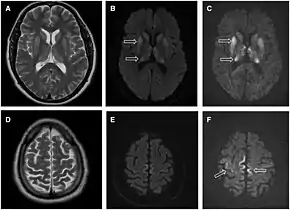

| Magnetic resonance image of sporadic CJD[2] | |

- MRI of the brain – often shows high signal intensity in the caudate nucleus and putamen bilaterally on T2-weighted images.

Imaging of the brain may be performed during medical evaluation, both to rule out other causes and to obtain supportive evidence for diagnosis. Imaging findings are variable in their appearance, and also variable in sensitivity and specificity.[41] While imaging plays a lesser role in diagnosis of CJD,[42] characteristic findings on brain MRI in some cases may precede onset of clinical manifestations.[43]

Brain MRI is the most useful imaging modality for changes related to CJD. Of the MRI sequences, diffuse-weighted imaging sequences are most sensitive. Characteristic findings are as follows:

- Focal or diffuse diffusion-restriction involving the cerebral cortex and/or basal ganglia. In about 24% of cases DWI shows only cortical hyperintensity; in 68%, cortical and subcortical abnormalities; and in 5%, only subcortical anomalies.[44] The most iconic and striking cortical abnormality has been called "cortical ribboning" or "cortical ribbon sign" due to hyperintensities resembling ribbons appearing in the cortex on MRI.[45] The involvement of the thalamus can be found in sCJD, is even stronger and constant in vCJD.[46]

- Varying degree of symmetric T2 hyperintense signal changes in the basal ganglia (i.e., caudate and putamen), and to a lesser extent globus pallidus and occipital cortex.[42]